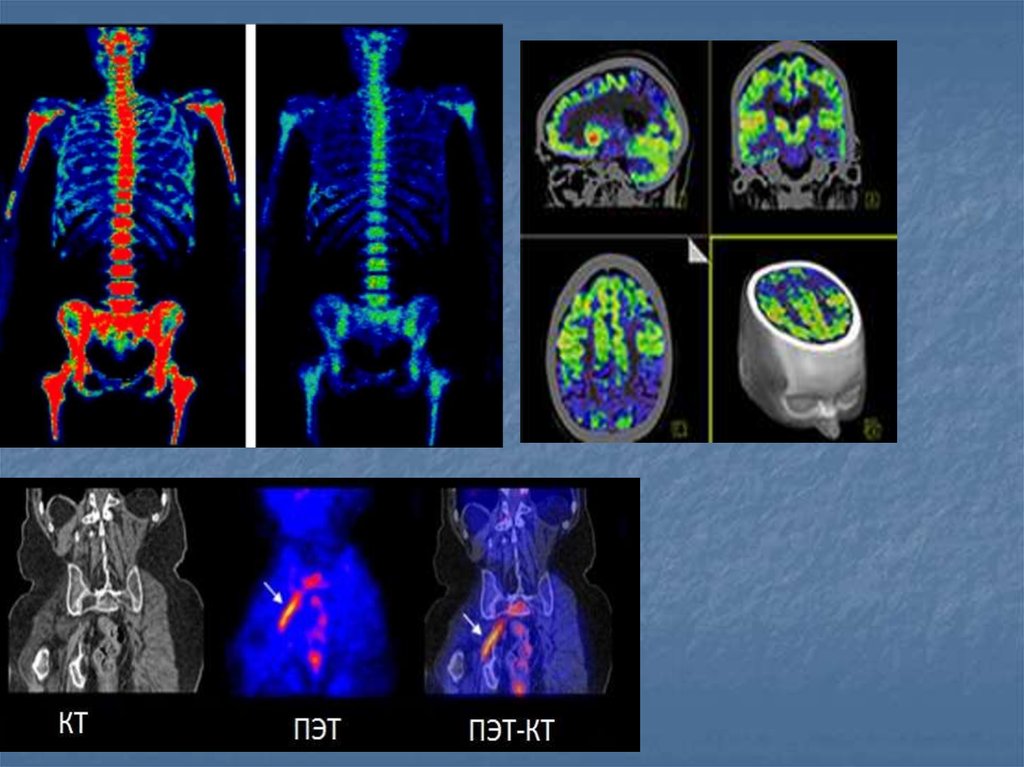

23. Показания

Опухоли различной локализации

Эпилепсия(определения очага)

Травмы головного мозга

Сосудистые нарушения головного мозга

Деменции

27. Показания

Диагностика ишемической болезни сердца (ИБС) в том числе

путём выявления преходящей ишемии миокарда, рубцовых

изменений, исследования сократительной способности сердца.

Диагностика тромбоэмболии лёгочной артерии.

Диагностика метастазов и первичных опухолей костной ткани,

переломов, воспаления, и инфекций (остеосцинтиграфия).

Исследование кровоснабжения головного мозга —

используется в диагностике болезни Альцгеймера, некоторых

форм деменции, инфекционных заболеваний. Существуют

маркеры, позволяющие проследить распределение

рецепторов некоторых нейромедиаторов в ткани мозга,

например, дофамина, что можно использовать в

диагностике болезни Паркинсона.

Диагностика заболеваний щитовидной и паращитовидной

желез.

Оценка функции почек и их кровоснабжения.

Выявление заболеваний печени, функциональных расстройств

гепатобилиарной системы.